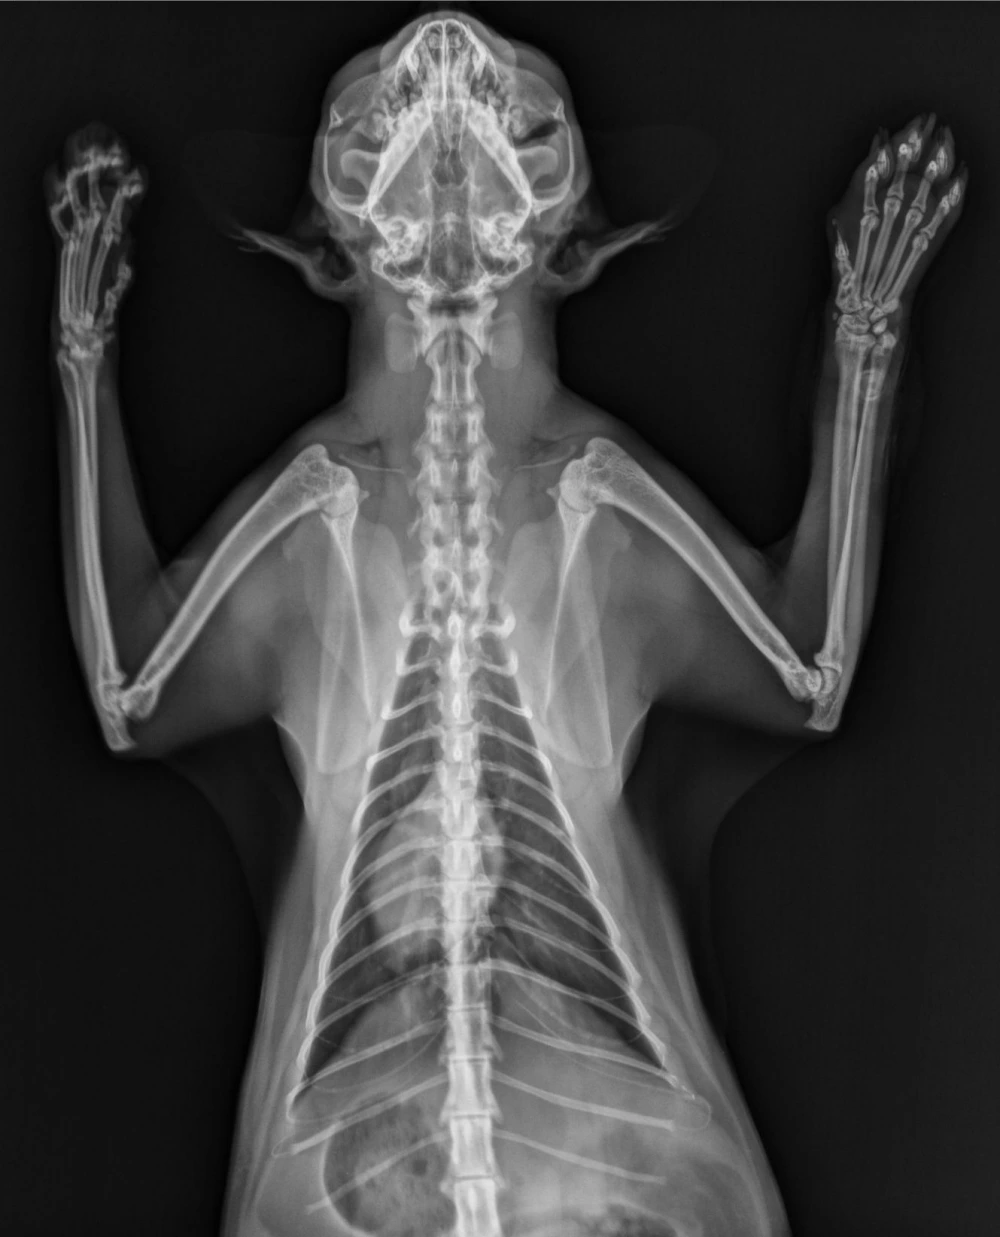

Os exames de raio x são uma ferramenta crucial para diagnosticar uma série de condições médicas em cães.

Com a radiografia, é possível visualizar estruturas internas do corpo do animal, como ossos, órgãos e articulações, permitindo identificar fraturas, lesões, tumores e outras patologias.

• Radiologia: Realização de radiografias digitais para análise detalhada do esqueleto e órgãos internos dos cachorros;